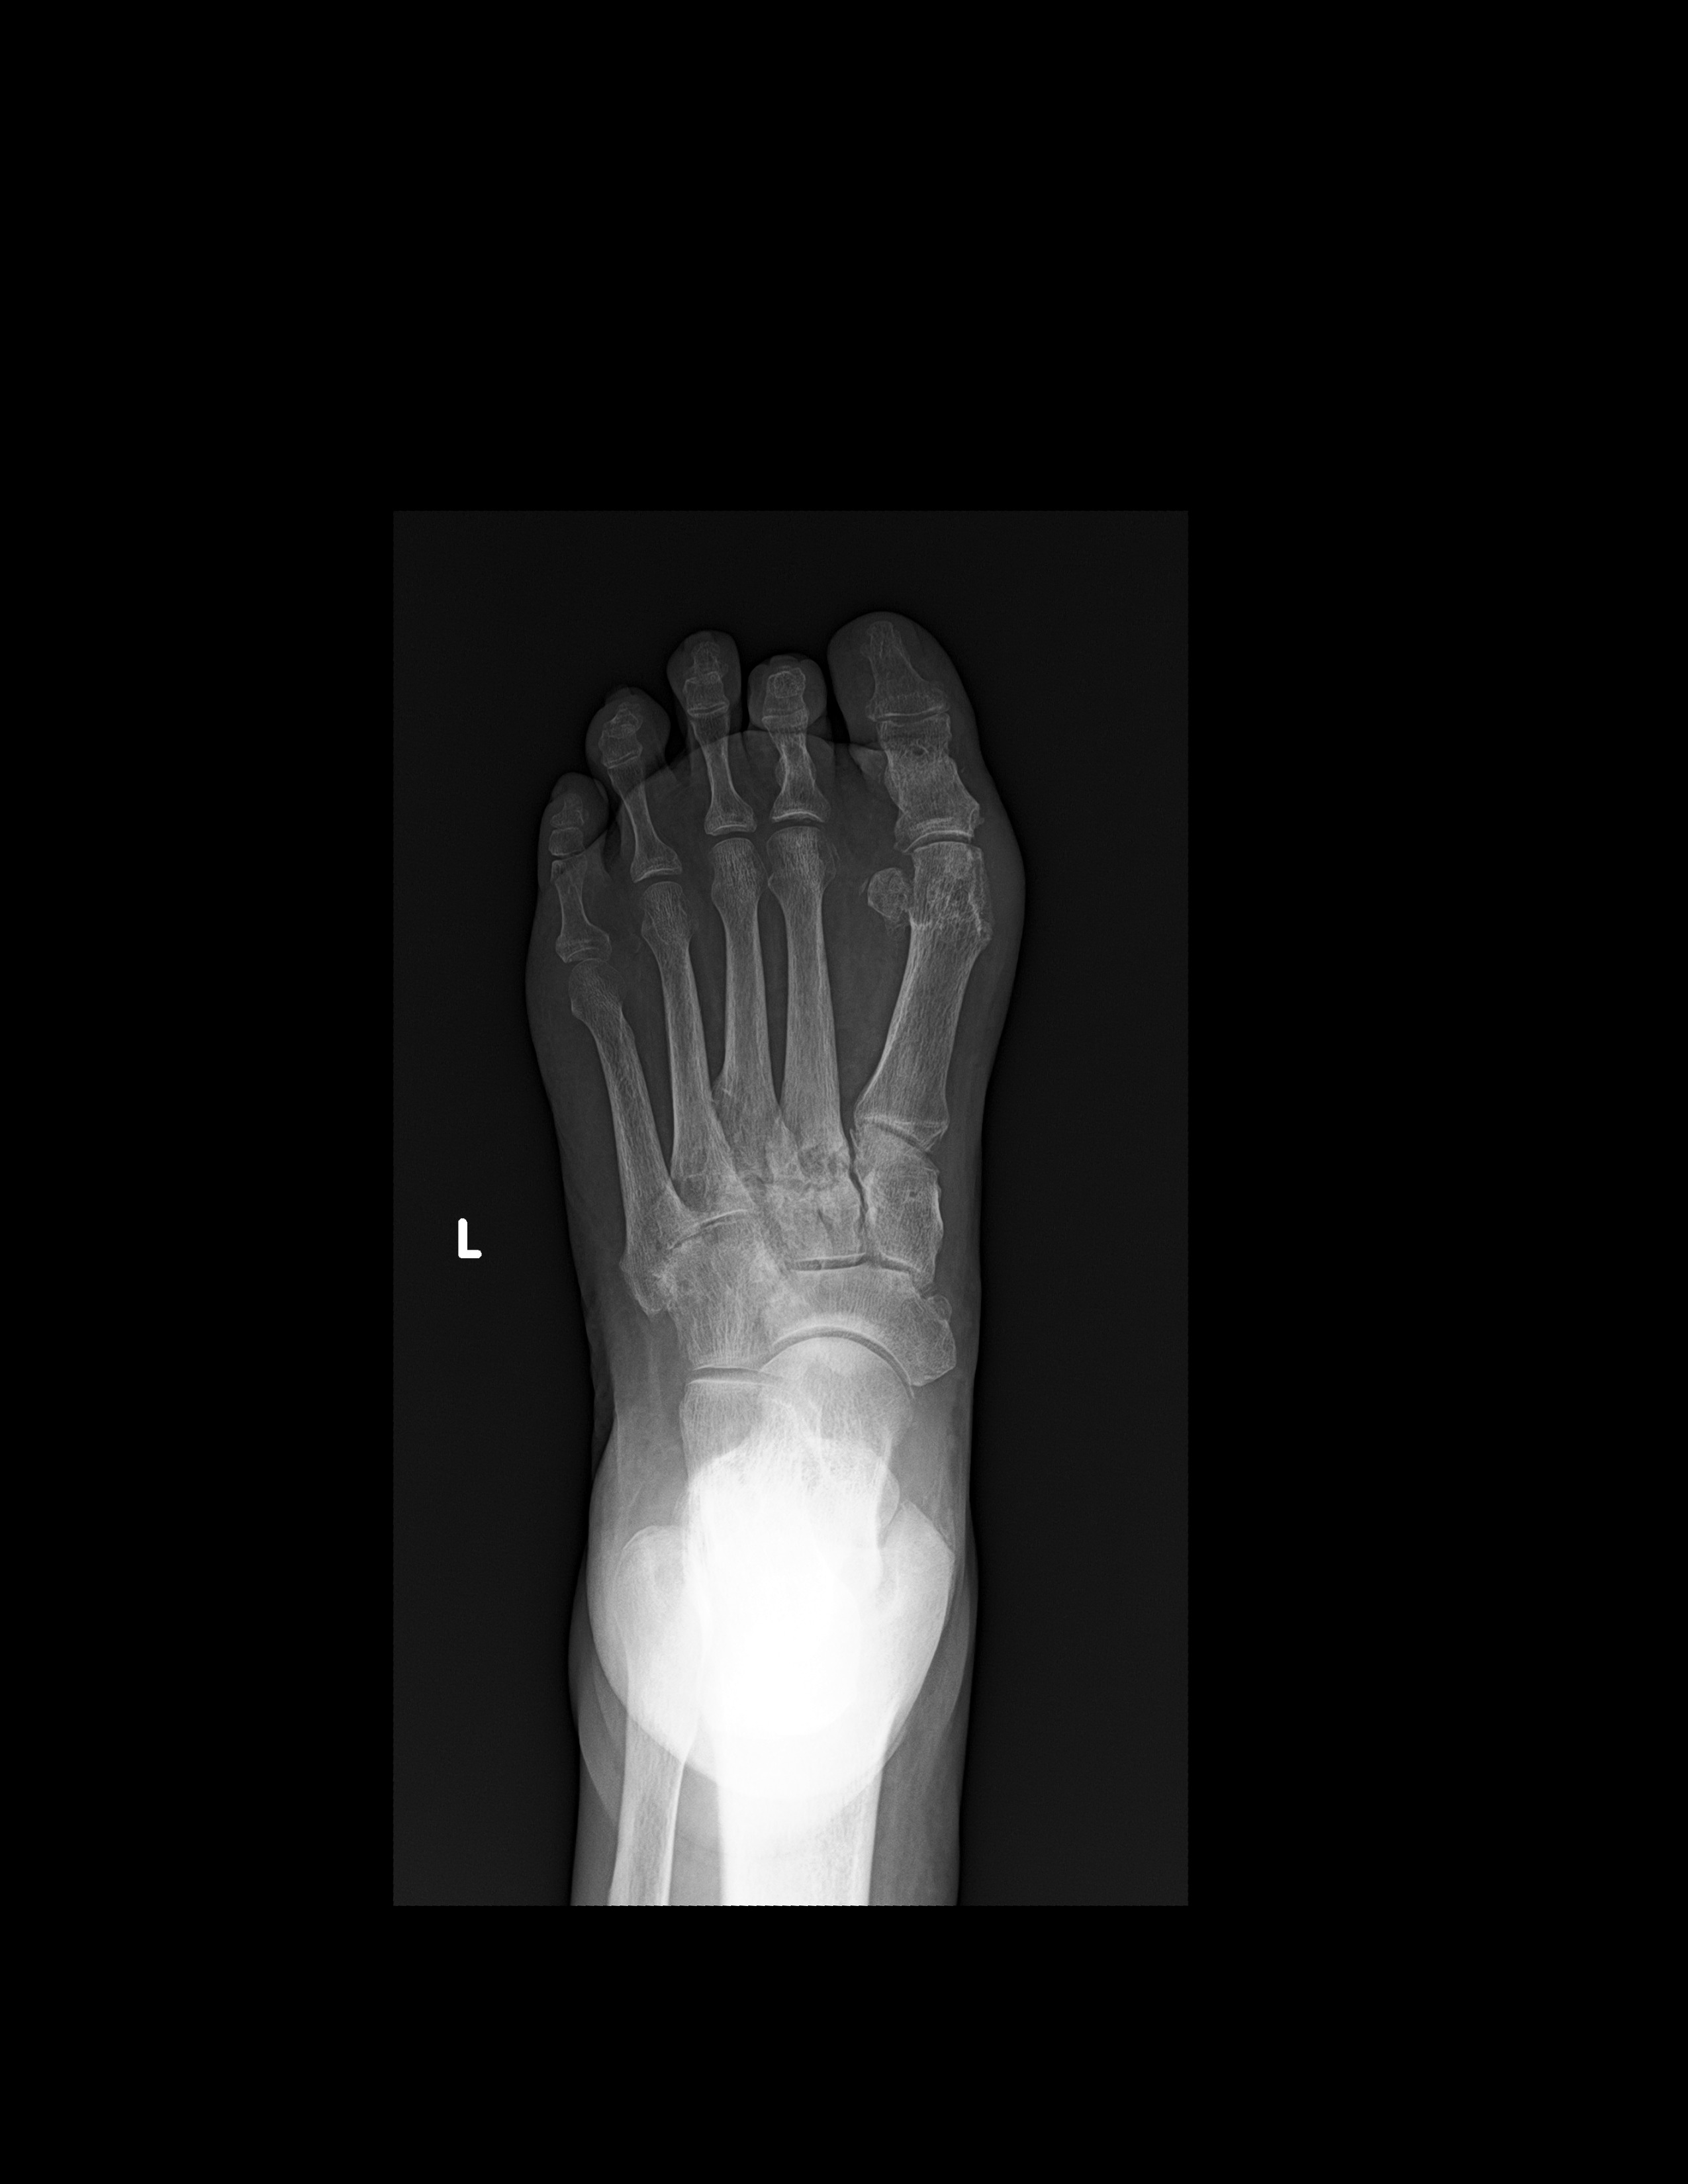

RADIOGRAFIA AP Y OBLICUA DE PIE

LAS PROYECCIONES RADIOLOGICAS OBTENIDAS NOS MUESTRAN LOS SIGUIENTES HALLAZGOS

-Se observa trayecto compuesto a nivel de proceso posterior del astrágalo. 2do cuneiforme con trazo longitudinal no desplazada. A nivel de base de 2do metatarso, con aparente fractura. Existe espícula osteofítica en porción inferior de tuberosidad del calcáneo. Resto de huesos del tarso, metatarsos y falanges, con disminución de la densidad, sin evidencia de lesiones líticas, blásticas o perdidas de la contigüidad.

-Angulo metatarsofalángico del 1er ortejo de 22.6°

-Angulo intermetatarsiano de 13.2°.

EN EL PRESENTE ESTUDIO RADIOGRÁFICO, EXISTE APARENTE FRACTURA DEL PROCESO POSTERIOR DEL ASTRÁGALO. FRACTURA DEL 2DO CUNEIFORME CON ASOCIACIÓN DE APARENTE FRACTURA NIVEL DE BASES DEL 2DO METATARSIANO, CON EDEMA ASOCIADO.

EXISTE ESPOLÓN ÓSEO DEL CALCÁNEO.

HALLUX VALGUS MODERADO.